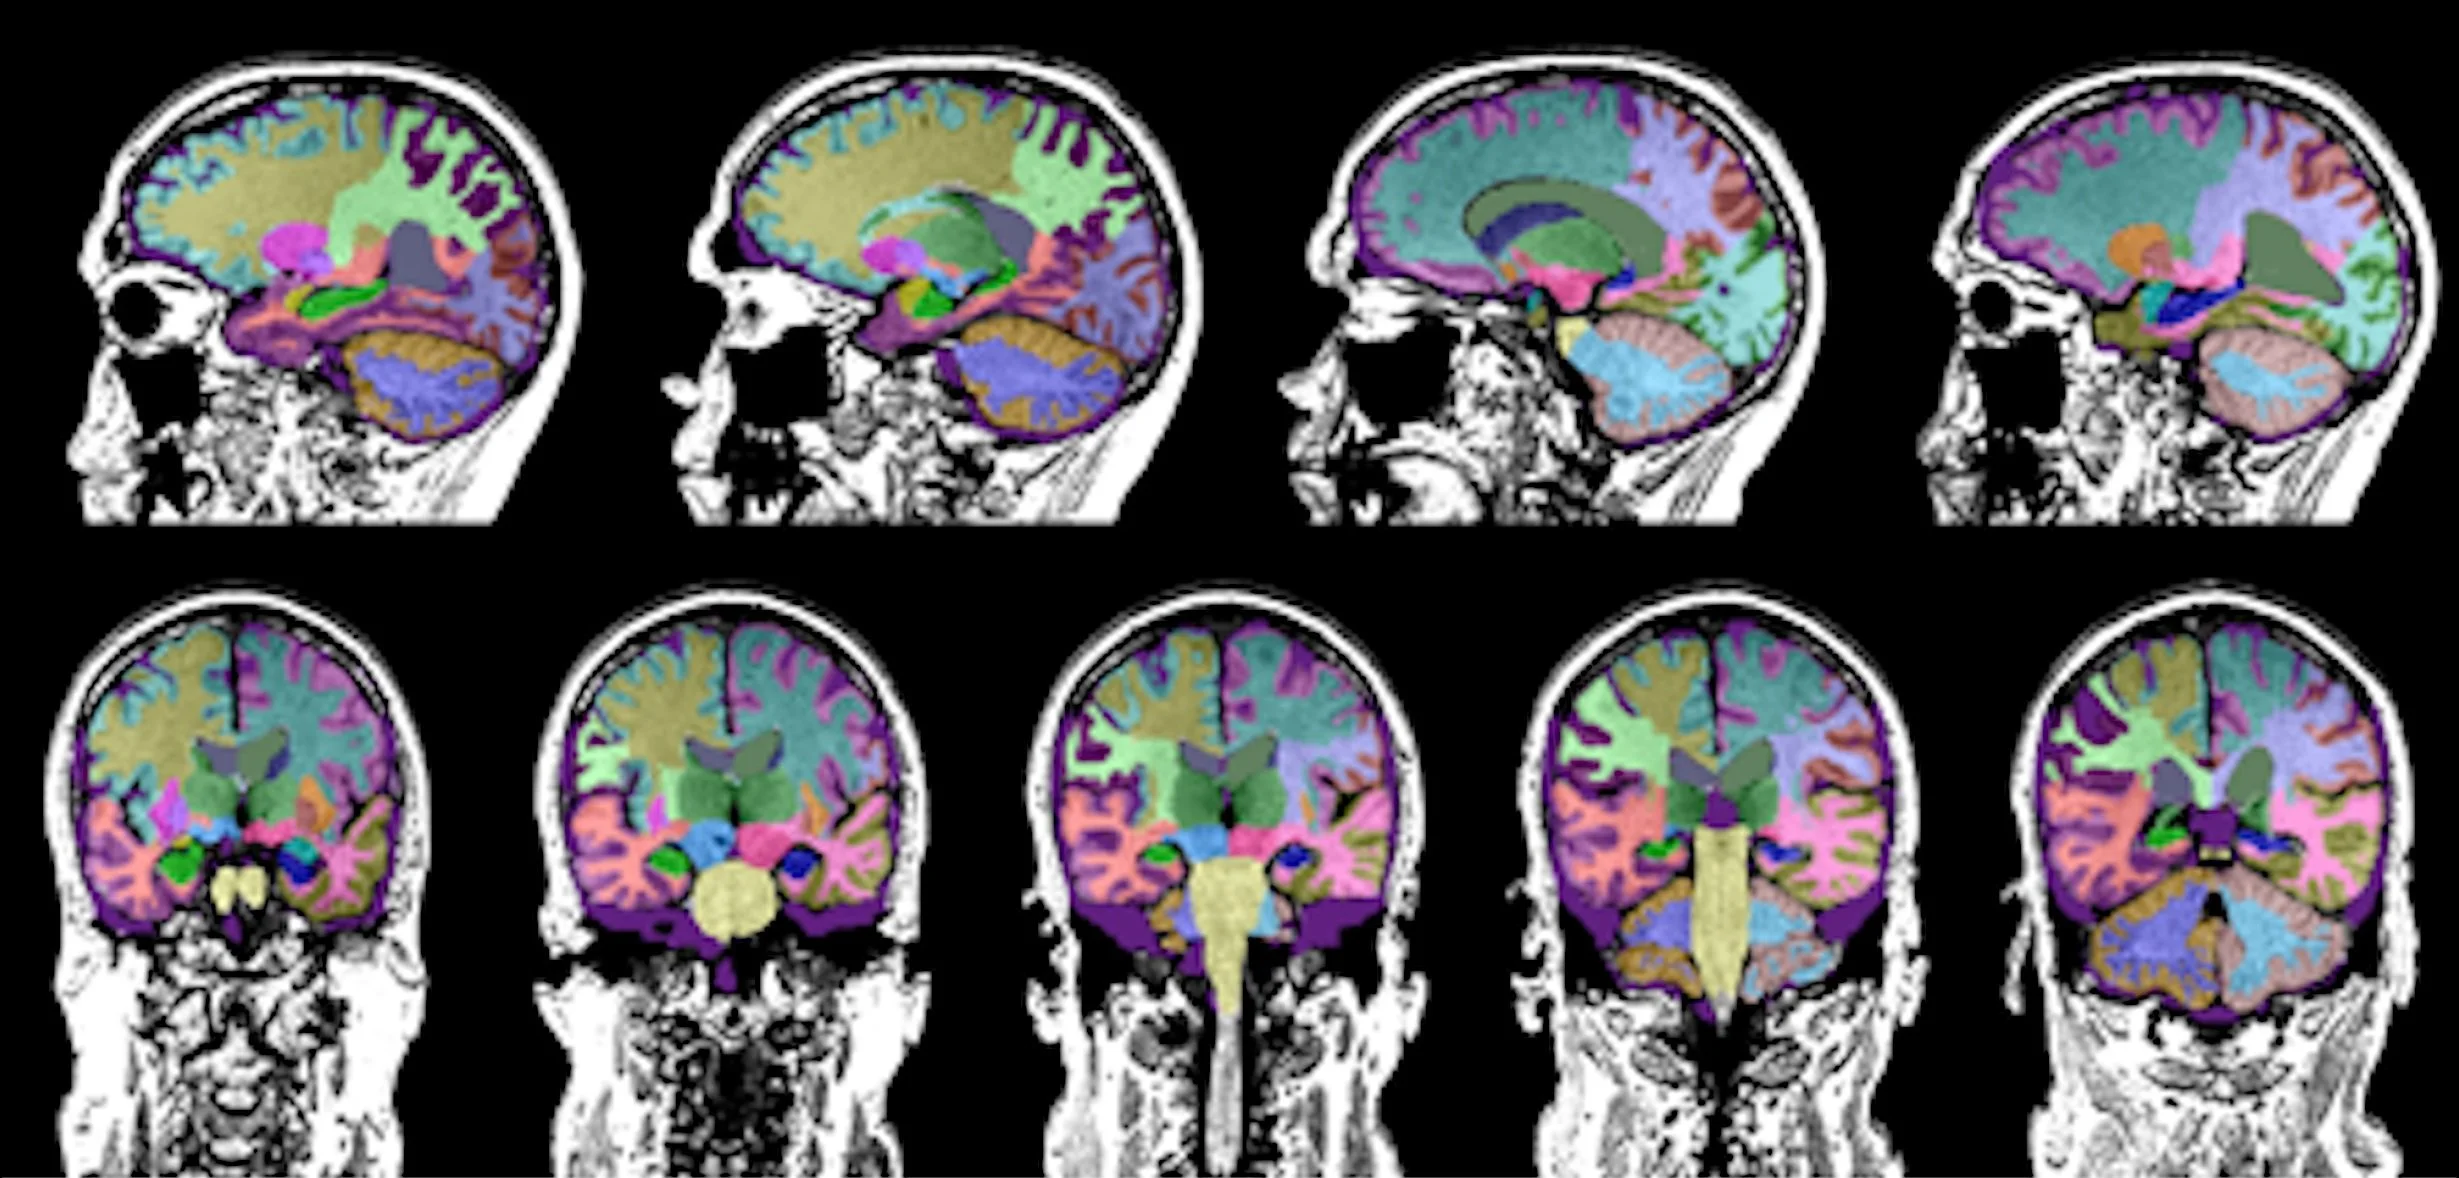

Los científicos han podido cuantificar el fenómeno gracias a un modelo de inteligencia artificial (IA) entrenado con más de mil variables obtenidas de resonancias magnéticas cerebrales. A partir de esos datos, calcularon lo que llaman la edad cerebral: una estimación de cómo de envejecido está un cerebro en comparación con la edad real de la persona.

La resonancia magnética nuclear permite estudiar el deterioro cognitivo asociado al envejecimiento y sucesos traumáticos. Cortesía: UCLA Health